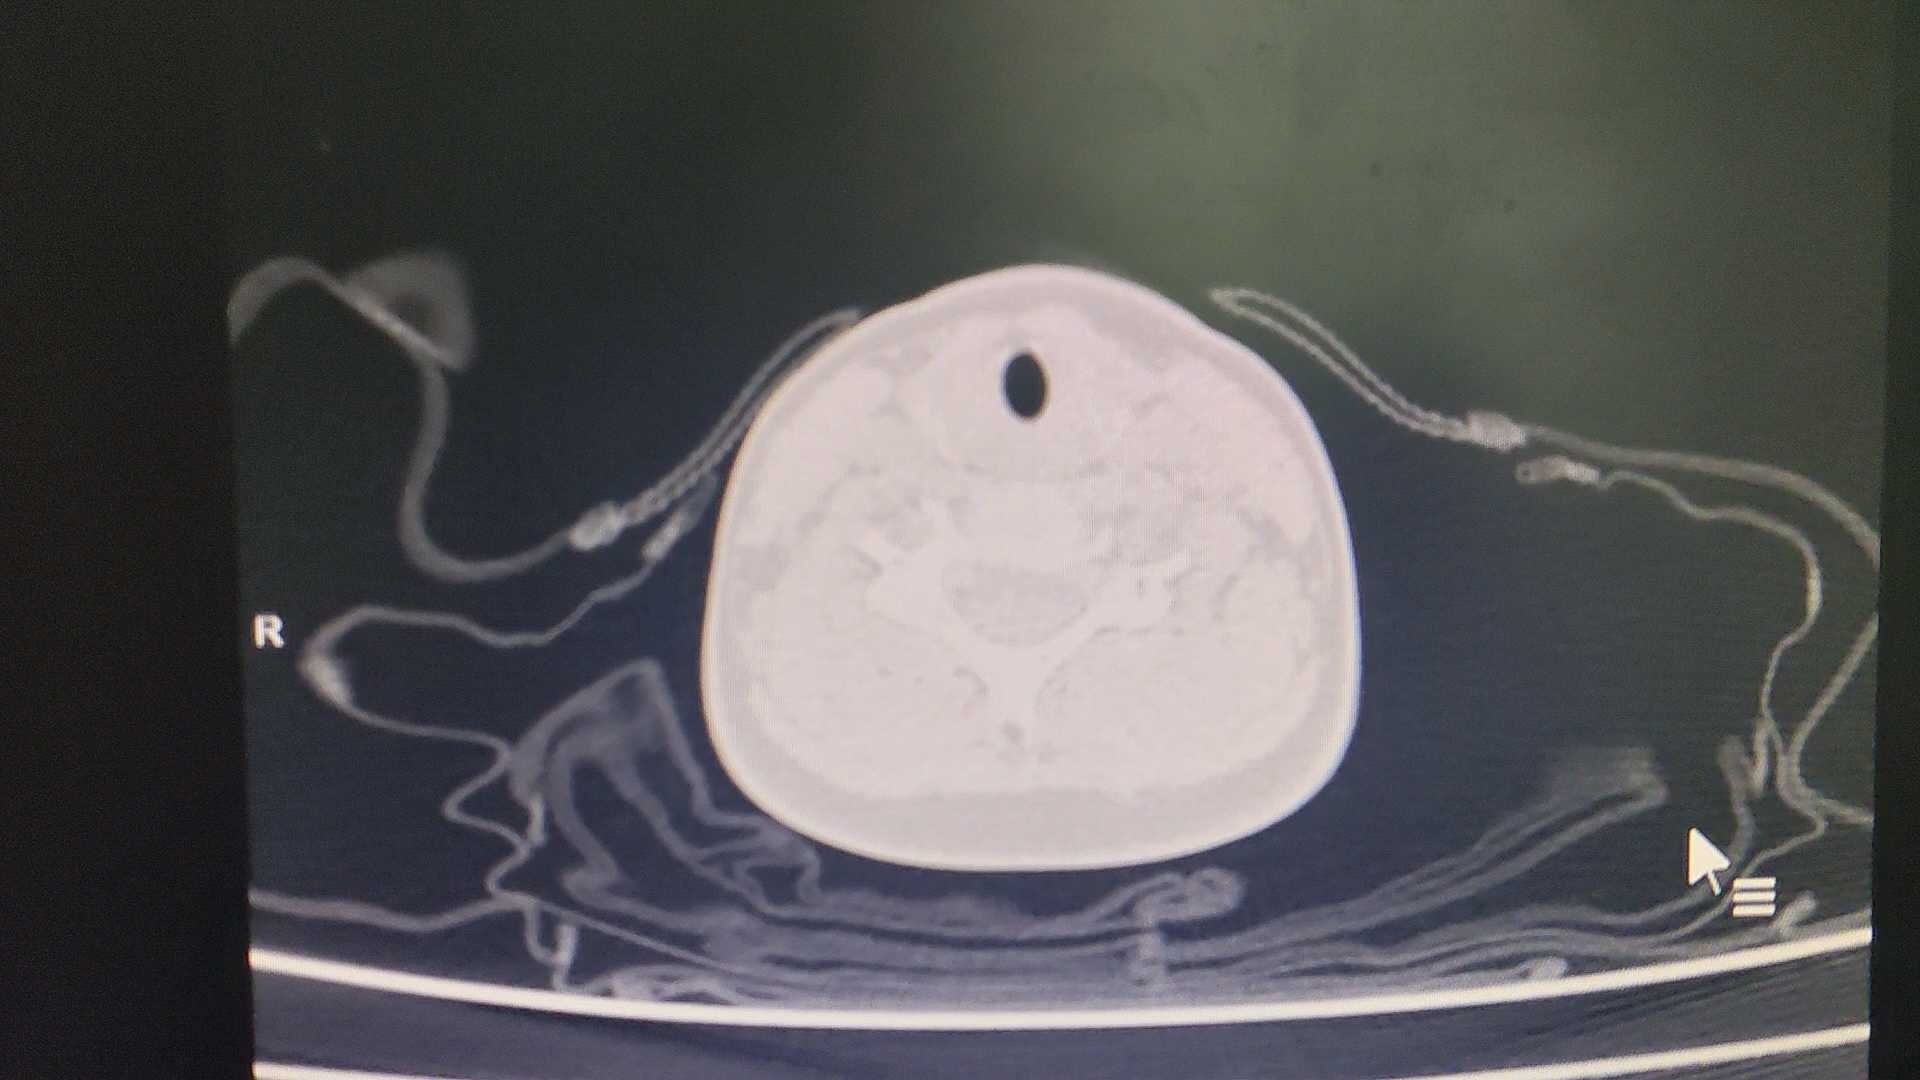

患儿,男,3岁8个月,以“咳嗽、发热5天。”为主诉入院;查体:T38.5℃,神志清楚,精神反应可,口周无发绀,咽部充血,双肺呼吸音粗、对称,可闻及湿罗音;心腹查体无特殊。辅助检查: